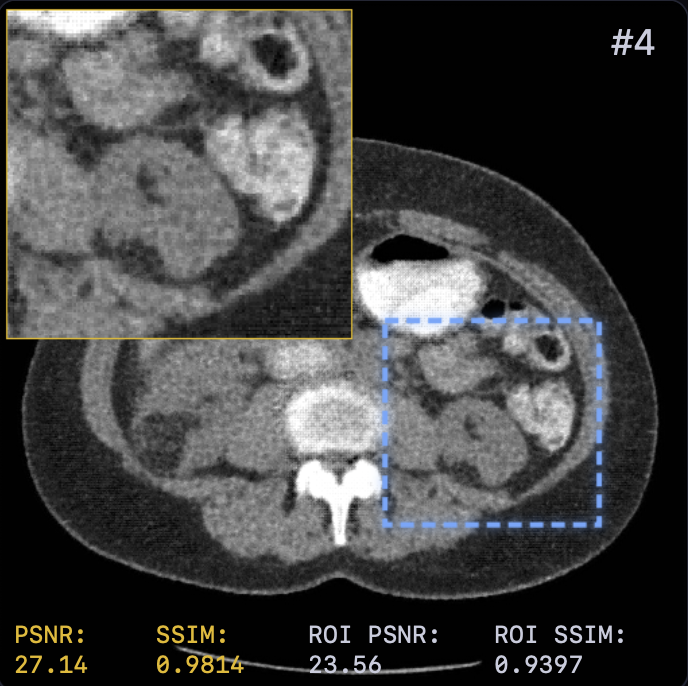

Table I presents the quantitative comparison. LTV achieves the best overall performance, surpassing FBP+U-Net [5] by approximately dB PSNR. Notably, learning the solver dynamics yields a consistent gain ( dB PSNR) over the fixed-solver baseline (29.42 vs. 30.15 dB). This confirms that end-to-end optimization of step sizes and relaxation provides modeling capacity beyond spatial adaptivity alone.

Qualitative results (Fig. 2) demonstrate that LTV preserves fine structures (e.g., vessel continuity) while avoiding the over-smoothing of classical TV and the anatomical inconsistencies of FBP+U-Net. This is corroborated by the error maps in Fig. 3, where LTV exhibits smaller and more spatially uniform residuals, indicating a balanced trade-off between noise suppression and detail preservation.